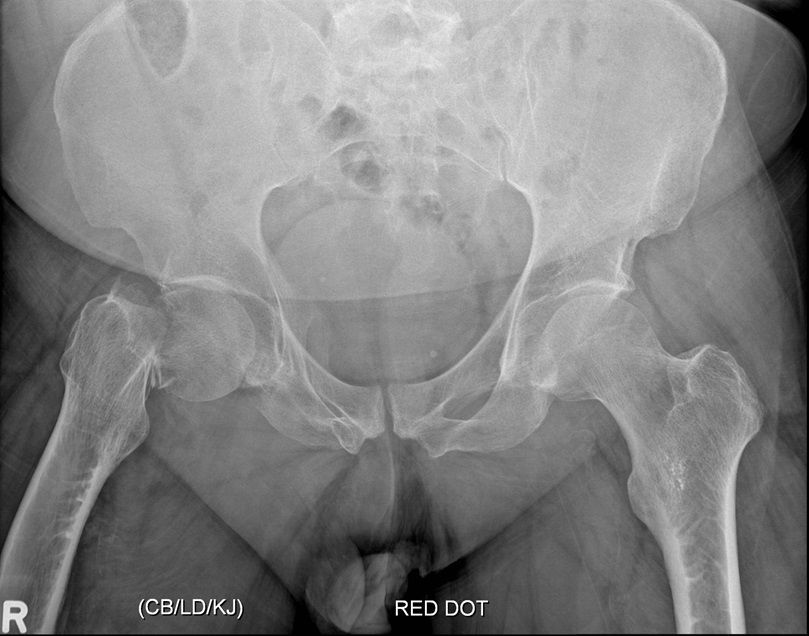

Question 4

Question

Which operation would you perform?

Answer

• THR

• Hemiarthroplasty